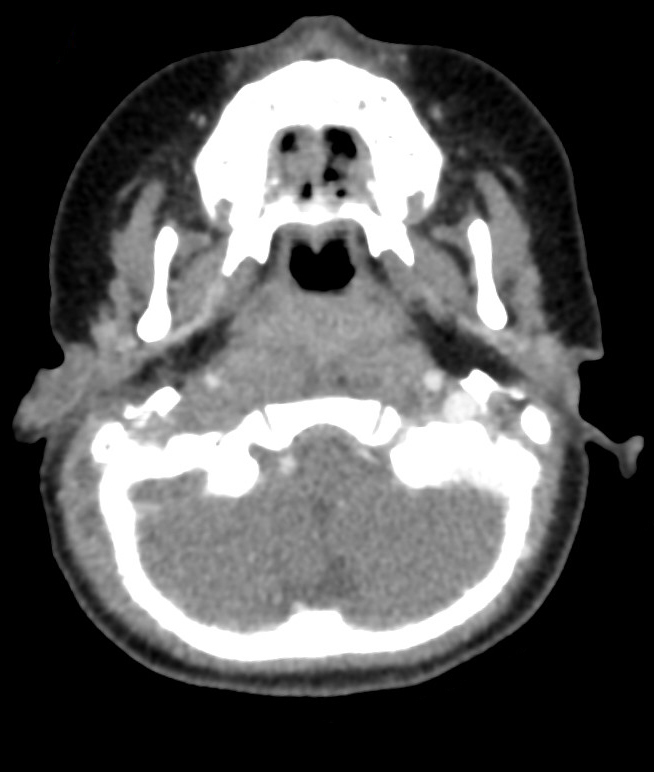

Voici l’imagerie que vous avez demandée. Devant le tableau, le radiologue a également choisi de faire une IRM.

Question 13 : Qu’en pensez-vous ?

Confirmée par la présence d’abcès sous-cutanés rétro-auriculaires droits (cf. question 4)

On voit bien une image plurilobée d’abcès à droite

On peut voir sur le scanner une image très hypodense dans le sinus à droite (alors que le sinus gauche est normalement hyperdense). C’est très visible sur la coupe en IRM avec un caillot hypo-intense au milieu du sinus veineux à droite

Comme expliqué à la question précédente, l’intérêt est de chercher les complications intracrâniennes. Il n’y a pas ici d’abcès intracrânien, mais on retrouve une thrombophlébite importante du sinus sigmoïde droit. Insérer image « Figure10.jpg ». Insérer image « Figure11.jpg ». Insérer image « Figure12.jpg »